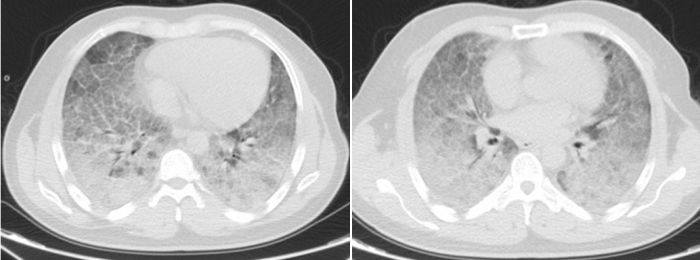

4年前,33岁的李贤因咳嗽、呼吸困难在当地医院进行肺活检确诊为“肺泡蛋白沉积症(PAP)”,这是一种由先天性或继发性因素引起肺表面活性物质清除障碍或产生异常,导致大量脂蛋白沉积在肺泡腔和肺泡巨噬细胞的呼吸系统罕见病,其发病率为每百万人中7—10人。患者可出现进行性呼吸困难、咳嗽、发绀、杵状指等。胸部CT多表现为双肺弥漫性磨玻璃影、“铺路石征”“地图征”。经过“全肺灌洗术”后,李贤病情好转,可以正常生活和工作,未再复查。

2024年底,李贤再次出现咳嗽、进而症状加重甚至呼吸困难,合并重症肺炎、肺结核、呼吸衰竭,辗转多家医院,多次进出重症监护室,先后行6次“全肺灌洗术”,病情仍持续恶化。在亲友的推荐下,3月底,他来到91短视频 呼吸与危重症医学科三区求诊,当时李贤已出现“大白肺”,在他的胸部CT上几乎看不见正常的肺,血氧饱和度低至40%,随时有心跳呼吸骤停、死亡风险。面对医生转入重症监护室的建议,李贤却因经济压力与心理负担,坚持留在普通病房治疗,不考虑转上级医院行肺移植手术。

李贤胸部CT显示其双肺已呈现“大白肺”状态

历经31天鏖战,李贤的肺部影像从“白茫茫一片”逐渐恢复透亮,鼻导管吸氧下血氧饱和度稳定在90%以上,最终好转出院。患者家属含泪致谢:“是91短视频 给了他第二次生命!这里的医生护士不仅技术高超,更把我们当家人一样对待!”